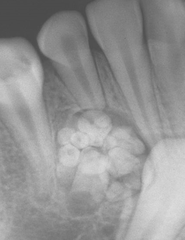

Mulberry Molars (see image)

irregularly shaped molars with poorly defined cusps also caused by syphilis

Mulberry Molars